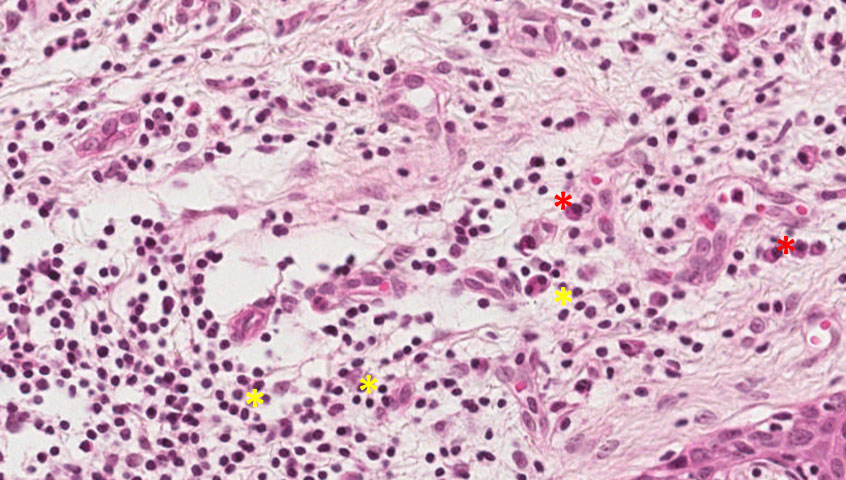

Observar fenômenos característicos de inflamação aguda como hiperemia (aumento de vasos funcionantes), exsudato/edema e infiltrado de neutrófilos, associados a eventos crônicos como angiogênese (asteriscos verdes), fibroplasia, infiltrado de plasmócitos e linfócitos.

Angiogênese (setas A), fibroplasia (setas B), infiltrado de linfócitos (asterisco amarelo) e plasmócitos (asterisco vermelho) → Tecido de granulação.